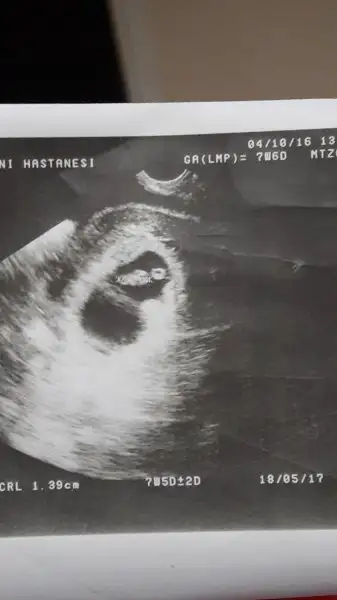

Kiz bence canim :)Merhaba kizlar .. Benimkine de bakar misiniz 8+6 yiz :)Havalianne__

Keseye gore erkek bebisin bence..Havalianne__ Benim ultrason resmime de cinsiyet yorumu yapar misiniz? Vajinal ultrason ve 8 haftalik.Eki Görüntüle 1892583

Merhaba kizlar .. Benimkine de bakar misiniz 8+6 yiz :)Havalianne__

Havalianne__ Benim ultrason resmime de cinsiyet yorumu yapar misiniz? Vajinal ultrason ve 8 haftalik.Eki Görüntüle 1892583